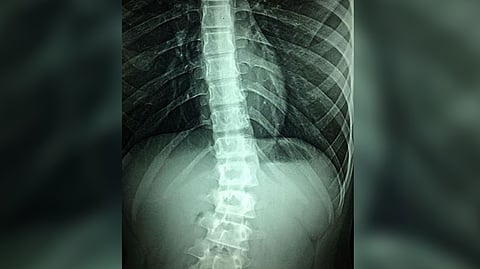

WASHINGTON: Currently, there are no effective treatments for spinal cord injury; physical rehabilitation can help patients regain some mobility, but the outcomes are severely limited in severe cases due to the failure of spinal neurons to regenerate naturally after injury.

Researchers led by Simone Di Giovanni at Imperial College London in the UK show that weekly treatments with an epigenetic activator can aid the regrowth of sensory and motor neurons in the spinal cord when given to mice 12 weeks after severe injury. The findings of the study were published in the journal PLOS Biology.